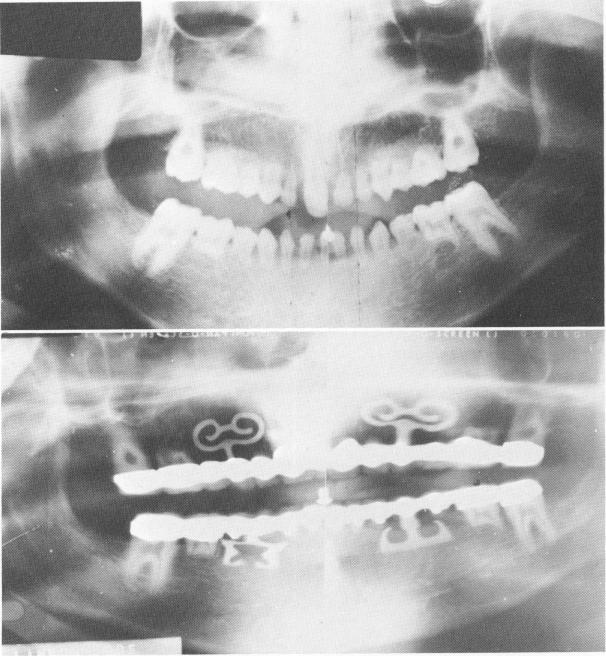

Fig. 15-89. A, A preoperative Panorex shows the only five permanent teeth. All others were deciduous. B, The Panorex of the completed case, showing the blades.

1 Panorex of completed case shows endosseous blade implants